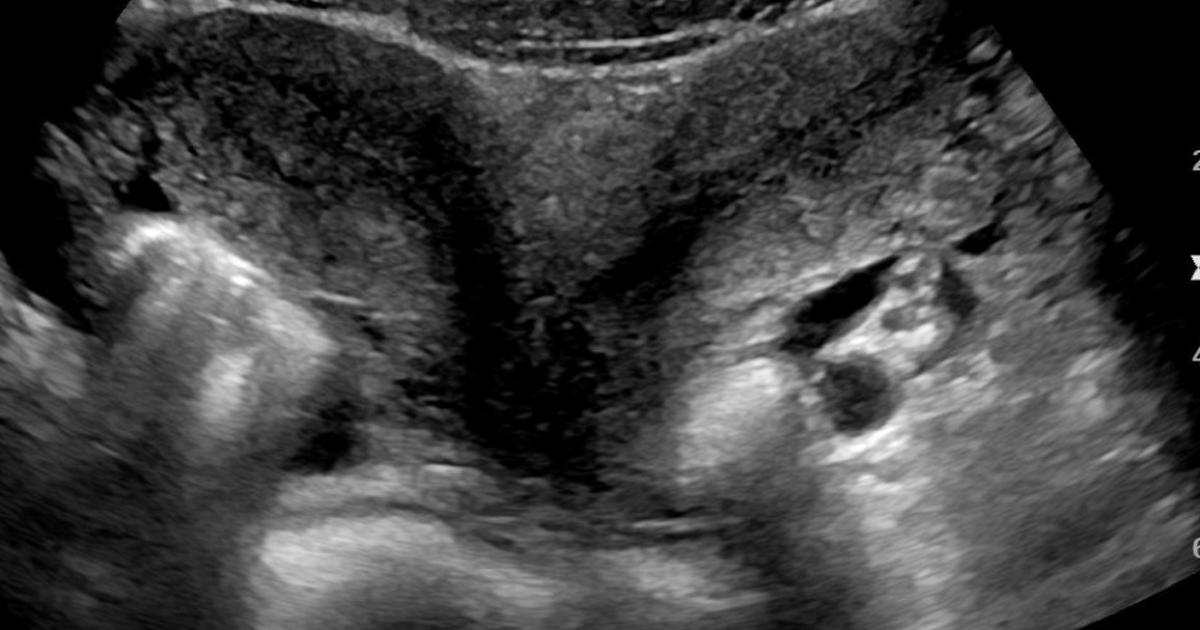

There are conditions that prompt duplications in the uterine, vaginal and cervical realms. The Müllerian duct reflects the precursor structures that embryologically morph to become the reproductive tract - when there is a deviation from normal development or a failure to fuse properly, anomalies arise. Müllerian duct anomalies (MDAs) can run in families and on one end of the spectrum can produce a double vagina, double uterus with dual cervices, aka Uterine Didelphys. This is the congenital anomaly being reported in this case.

Such atypical pelvic organs can result in several varieties (e.g. double uterus, single vagina or double everything). These are often diagnosed upon first menstruation or when issues with fertility come into play. With the former, one vaginal canal might end in a blind pouch so blood will accumulate with an inability to flow out of the body and great discomfort will arise. Upon investigation and proper medical evaluation, the discovery will be made. The latter reality might also lead to determining such an underlying cause.